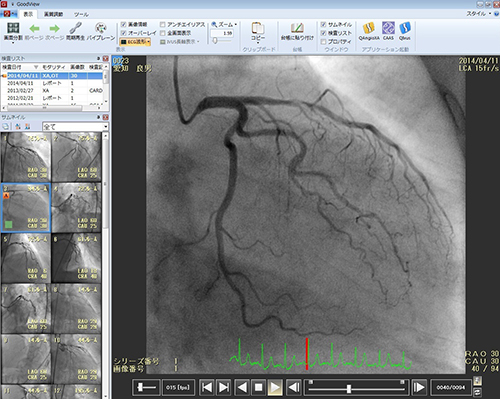

DICOMビューワ 「GoodView」は,アンギオ像の自動Biplane表示,IVUS像の長軸比較表示等,モダリティそれぞれの特性に応じた表示機能を搭載しており,Singleframe DICOMのCT,MR像の参照表示も含めてマルチにご活用いただけます。直感的な操作が可能なGUIや,検索画面に戻らずともビューワ上でその患者様に紐付く他検査の画像が参照できる機能など,快適な操作性を提供し,さらに専用端末用と専用端末以外で閲覧するためのWebビューワの操作性を統一させました。またアノテーションやフレーム編集処理を施した後に各種動画・静止画フォーマットへ変換する資料作成に欠かせない機能も搭載しています。「GoodView」はこれらネットワークシステム用ビューワの他に,Windows,iOS上で単独でお使いいただける製品もラインナップしています。

GoodView:動画像ビューワ